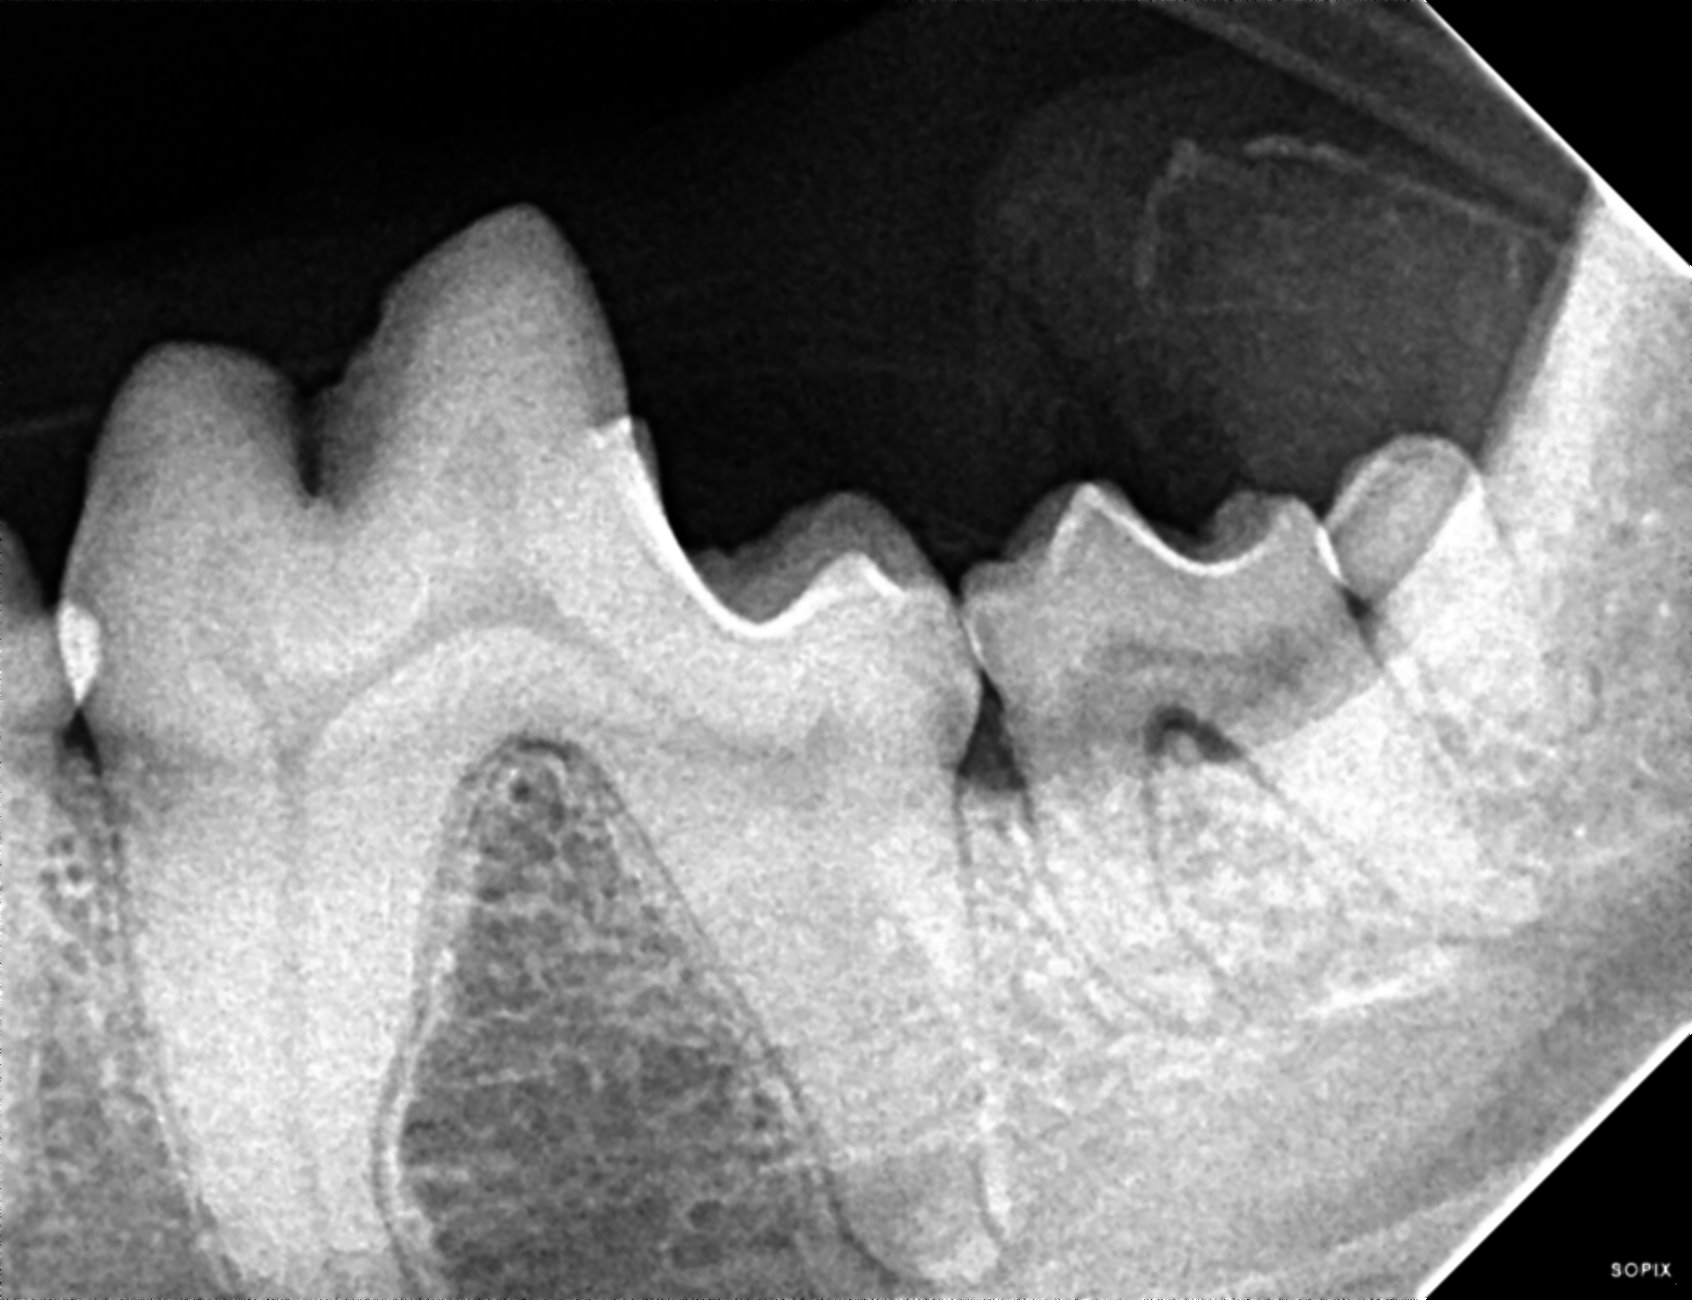

The prophylactic dental includes x-rays of all the teeth, ultrasonic scaling of the plaque and tartar from the teeth, polishing, and fluoride treatment. It is impossible to determine the full extent of dentistry your pet needs until they are under anesthesia and we can examine each tooth individually, but we can give an estimate of your pets dental status and needs during your routine exam.